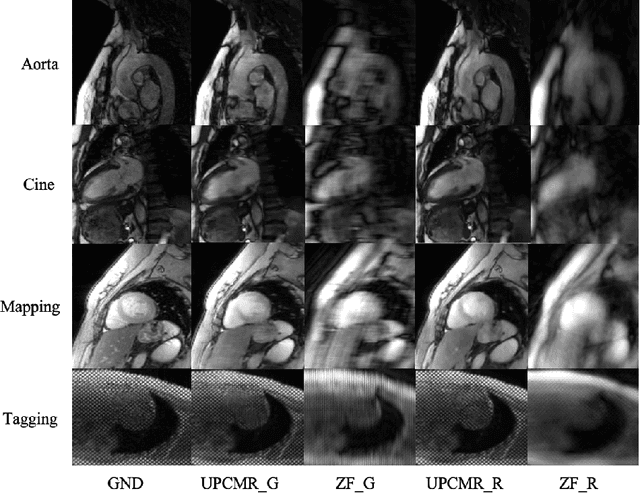

Abstract:Cardiac magnetic resonance imaging (CMR) is vital for diagnosing heart diseases, but long scan time remains a major drawback. To address this, accelerated imaging techniques have been introduced by undersampling k-space, which reduces the quality of the resulting images. Recent deep learning advancements aim to speed up scanning while preserving quality, but adapting to various sampling modes and undersampling factors remains challenging. Therefore, building a universal model is a promising direction. In this work, we introduce UPCMR, a universal unrolled model designed for CMR reconstruction. This model incorporates two kinds of learnable prompts, undersampling-specific prompt and spatial-specific prompt, and integrates them with a UNet structure in each block. Overall, by using the CMRxRecon2024 challenge dataset for training and validation, the UPCMR model highly enhances reconstructed image quality across all random sampling scenarios through an effective training strategy compared to some traditional methods, demonstrating strong adaptability potential for this task.